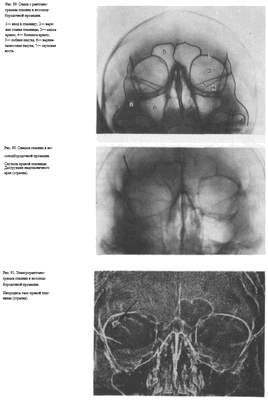

Рентгенологическое исследование лицевого скелета включает рентгенографию глазницы и ее содержимого, придаточных пазух носа, прицельные снимки отдельных костей лицевого скелета и снимки зубочелюстного аппарата. Большинство анатомических образований лицевого скелета достаточно четко видно на обзорных снимках черепа в прямой передней и задней проекциях, на снимках в носоподбородочной, подбородочной, носолобной, лобной, боковой и аксиальной проекциях.

УКЛАДКИ СНИМОК ГЛАЗНИЦЫ В НОСОПОДБОРОДОЧНОЙ ПРОЕКЦИИ

Назначение снимка. Изучение состояния костей, образующих вход в глазницу, костной структуры верхней и наружной ее стенок.

Укладка больного для выполнения снимка сходна с укладкой для выполнения обзорного снимка в этой же проекции. В данном случае используюткассету размером 13X18 см, располагая ее в кассетодержателе в поперечном положении. Больной прилежит к столу подбородком и кончиком носа,переносье соответствует центру кассеты. Центральный пучок излучениянаправляют на центр кассеты. Фокусное расстояние—100 см.

В этой же укладке может быть выполнен снимок одной (правой или левой) глазницы. В таких случаях центр снимаемой глазницы соответствует центру кассеты, и на него отвесно направляют пучок излучения, используя тубус или диафрагмирование пучка излучения с помощью щелевой диафрагмы. Фокусное расстояние—100 см (рис. 88).

Информативность снимка. На снимке хорошо видны вход в глазницу, структура ее стенок, иногда малое и большое крыло клиновидной кости (рис. 89). На снимке в этой проекции могут быть выявлены деструктивные изменения стенок глазницы и инородные тела в ее полости (рис. 90, 91). Для выявления изменений в области верхней стенки глазницы (например, при

На прицельном снимке каждой из глазниц в этой же проекции, как правило, небольшие изменения структуры стенок, а также мелкие инородные тела глаза видны лучше. Такие снимки широко используют в офтальмологической практике (рис. 92).